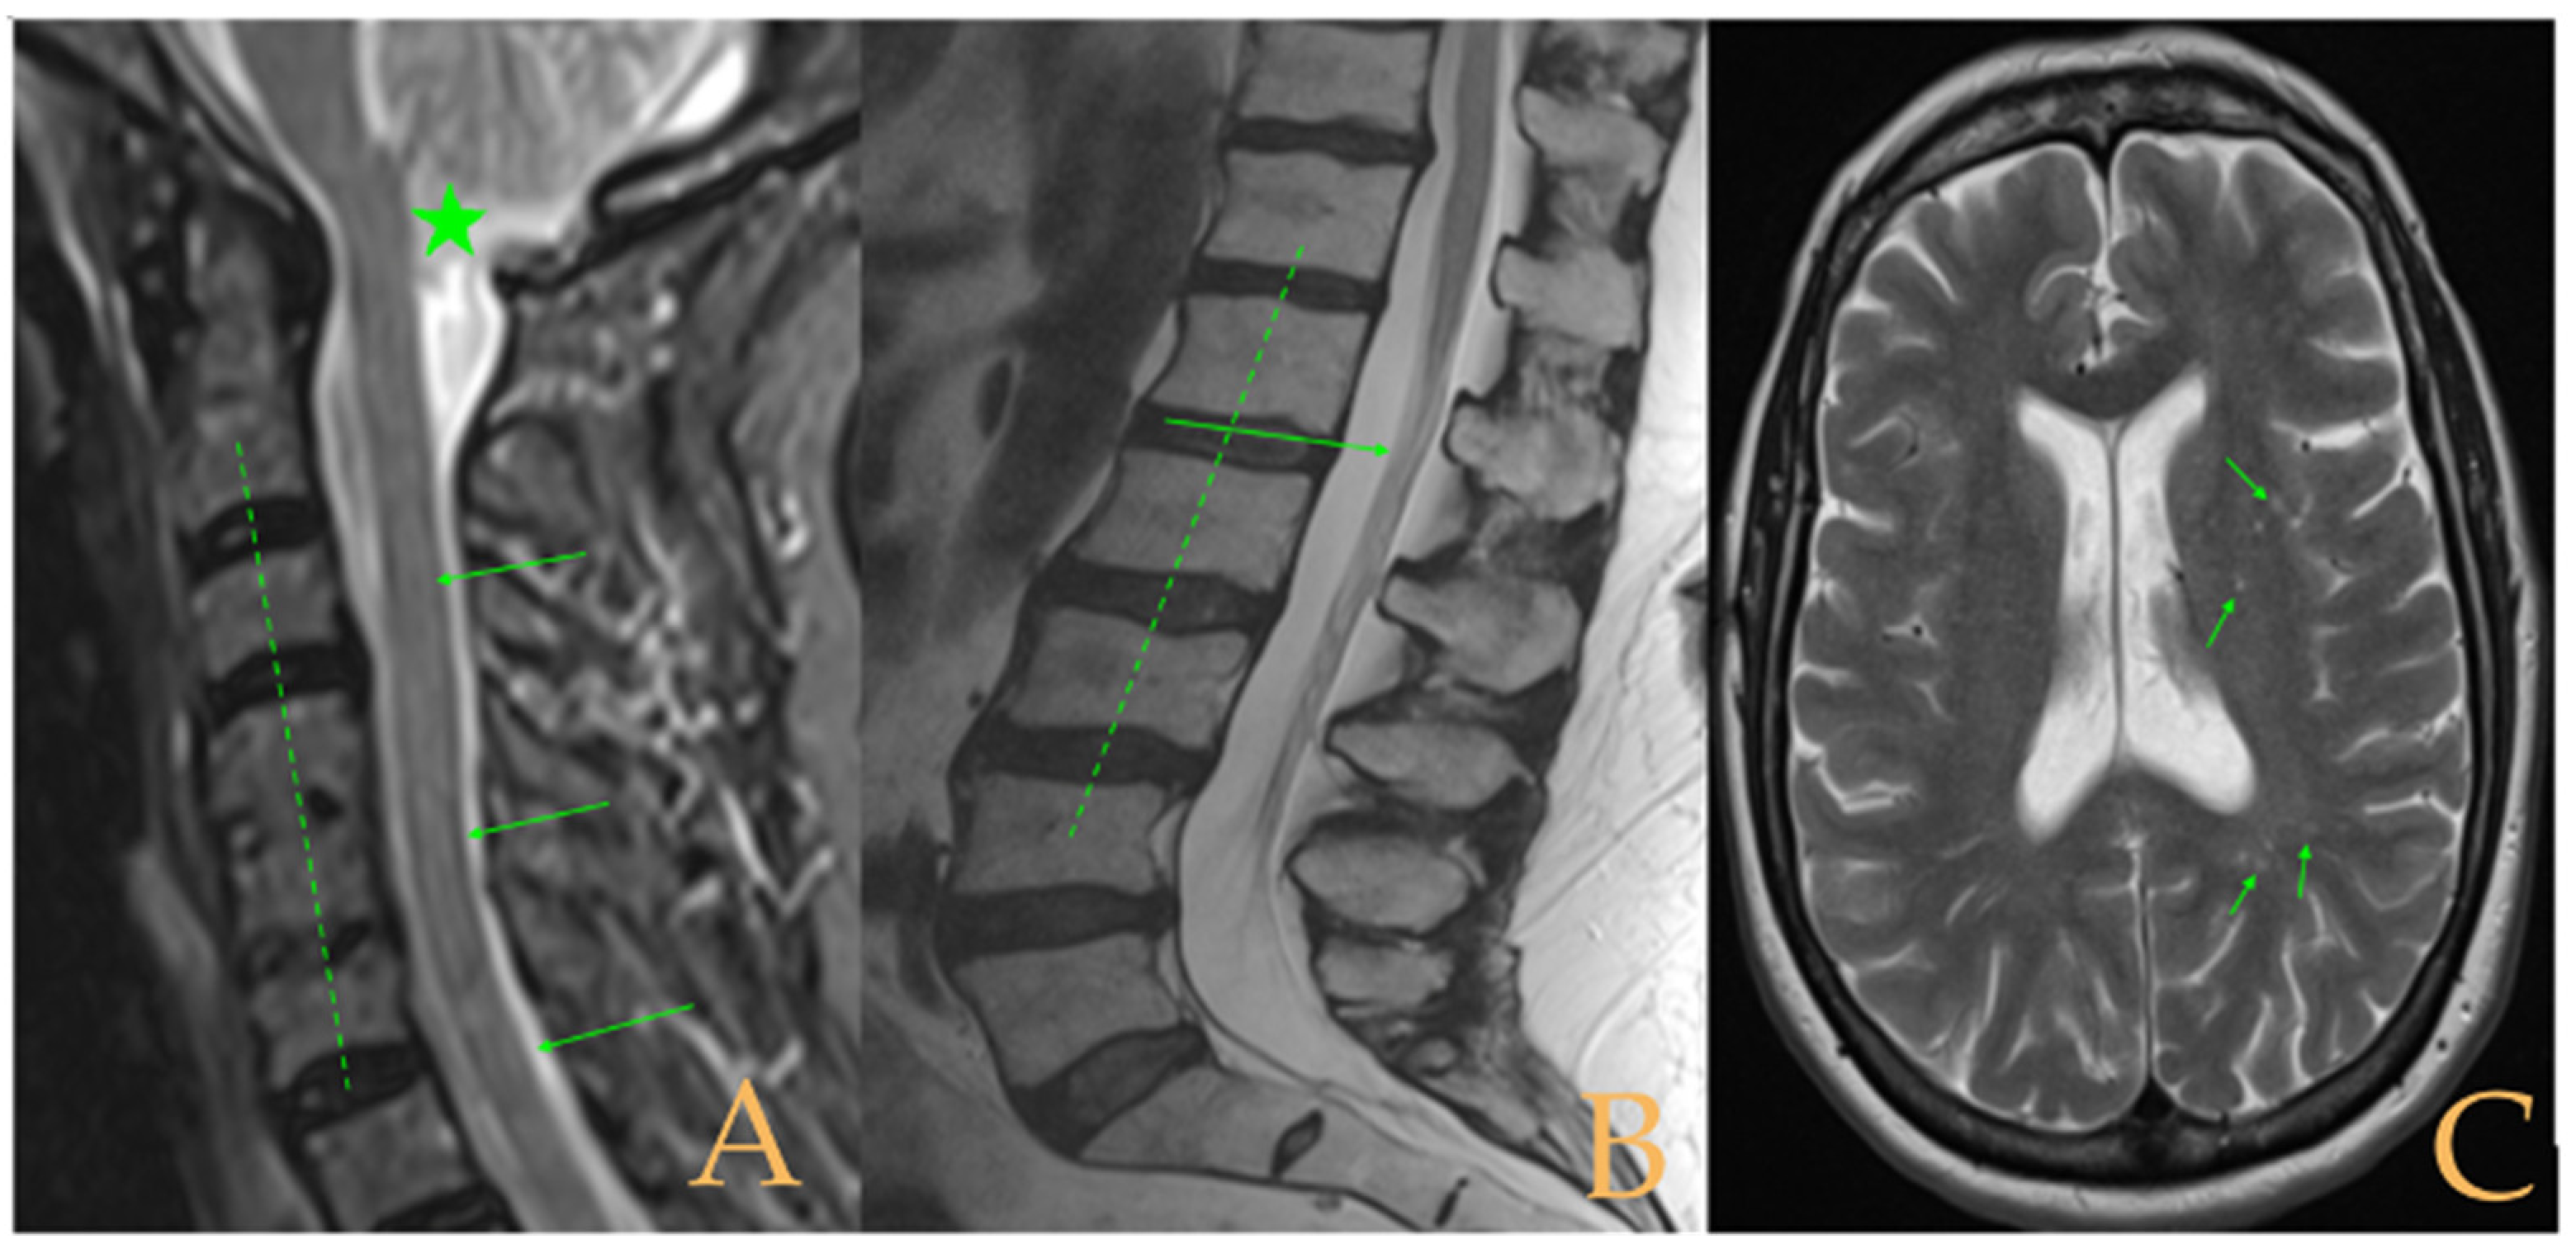

The MRI showed a descent of the cerebellar tonsils, increased supracerebral space, and micro lacunae in the bilateral white matter and the left basal ganglia. Upper cervical kyphosis and straightening in the lower levels. Surgical arthrodesis at C4-C5 and C5-C6. Cervical, thoracic and lumbar protrusions. Ischemia and oedema in the cervical and thoracic spinal cord. Slight cervical rotoscoliosis. Disc protrusions: T7-8, T11-L1, L2-L3-L4, and disc herniation L4-L5. Loss of the lumbar lordosis. Conus medullaris at the level of the middle third of the L1 vertebra (Figure 2). The X-ray images of the entire spine showed levoconvex thoracolumbar scoliosis of 21°, dysmetria of the lower extremities with shortening of the right lower extremity by 10 mm, with respect to the level of the hip, and 99 mm at the level of the iliac crests, 16° cervical lordosis, 49° thoracic kyphosis, and 59° lumbar lordosis.

Figure 2.

Imaging of patient 2. A: Image suggestive of spinal cord ischemia (arrows), impaction of the cerebellar tonsils (star), and straightening of the cervical spine (interrupted line); B: straightening of the upper part of the lumbar spine (interrupted line) and conus medullaris at the level of the L2L3 disc space (arrow); and C: brain MRI with micro lacunae in the white matter (arrows).